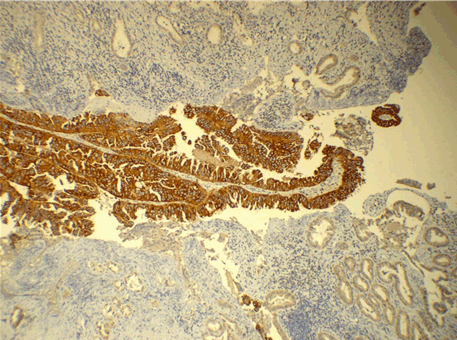

Figure 1: Photomicrograph showing strong and diffuse 3+ positivity of Her2/neu in Gallbladder Carcinoma (x100).

Pyloric metaplasia, intestinal metaplasia and dysplasia were seen in 39 (72%), 32 (59%) and 24 cases (44.44%), respectively. Maximum cases in our study were in stage T2 at the time of diagnosis and most of them were moderately differentiated carcinoma. Carcinomas detected incidentally were mostly in the early stages of cancer (T1). Her2/neu was strongly positive (3+) in five cases (9.25%) and moderately positive (2+) in 14 cases (25.92%). There was a lot of heterogeneity in the expression of Her2/neu showing 1+ and 2+ positivity in different areas. No correlation was seen between IHC staining pattern and tumor grade (Table 1), but frequency of Her2/neu positive cases was highest in advanced stage (p = 0.042) (Table 2).

In our study, one case each of well differentiated and a poorly differentiated tumor, showed sharply defined 3+ positivity adjacent to 1+ positive area. Also there were few cases in which focal 2+ positive areas were present adjacent to predominant 1+ positive area. This suggests that even in a single case of GBC, different staining patterns of Her2/neu can be seen which highlights the importance of adequate sampling of the tumor for Her2/neu immunostaining. To the best of our knowledge, such a heterogeneous pattern of immunostaining of Her2/neu has never been reported in literature prior to this study.